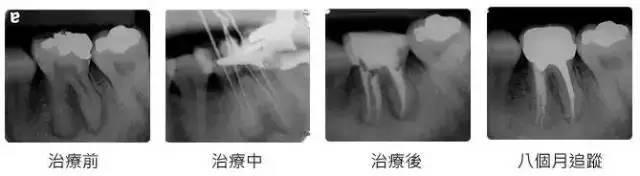

现在很多人都会蛀牙,然后很多人发现蛀牙的时候,往往都是比较严重了,需要进行根管治疗——也就是要截取牙神经。

1、一般根管治疗后都是建议要套一个冠。根管治疗后套冠是为了保护失去活力的牙齿,防止牙齿崩裂。

3、定期口腔检查,每半年或者一年检查根管后牙齿的情况,根管后根尖的状况。